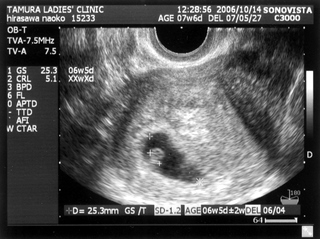

5ヶ月(18週と5日) 体重:262g BPD(頭を上から見た耳から耳の幅のような感じ):46.8㎜ FTA(お腹の断面):15.9平方㎝ FL(大腿骨長 太ももの骨の長さ):22.7㎜ 6ヶ月(22週と5日) 体重:602g BPD(児頭大横径 頭を上から見た耳から耳の幅のような感じ):57.6㎜ FTA(体幹横断面 お腹の断面):26.6平方㎝ FL(大腿骨長 太ももの骨の長さ):38.1㎜ まだこの頃は顔と上半身が収まっていました。 検診は妊娠23週までは、4週に一度なのでドキドキとワクワクです。 ちゃんと成長してるかなあなんて考えて行って、 心音をきいたり、エコーを見て毎回安心と喜びがわいてきます(*^_^*) たった4週で、体重は3倍近くにも!かわいいなあ☆ 6ヶ月の検診日ダンナっちは仕事だったから、 エコー写真を携帯で撮って送ると、 『目ん玉でてない!?』 と返事が返ってきました。 眼球がそう見えるんだろうけど、目のとても細いダンナっちには 衝撃的だったんですね(^。^;) 胎動を初めて感じた日をわたしはわかりません・・・ メモにとるなり、日記にかくなりすることをすっかり忘れてしまって、 今となって後悔<<o(>_<)o>> ダメな母親めっ と思いつつも、わたしらしいと感じ笑っています(^_^;) 12月の末に友達に、 「腸の動きか!?って思うのはあるんだけどまだよくわかんない」 と言ったのを覚えているので、12月の終わりから1月にかけての あたりなんでしょうね。 いつの間にかポッコポッコしていました! ベイビーこんなママだけどよろしく└|∵|┐♪┌|∵|┘ 6ヶ月までは、普通にそれまで履いていたジーンズも入っていたんだけど、 6ヶ月終わるころには、急に入らなくなってビックリしました~ 食生活の変化も特になかったです。 あ、ポテトチップスあまり自分で 買わなかったのに、1週間くらいブームの時期がありました!妊娠による影響かな!? 今、ベイビーはしゃっくりをしているみたいです |